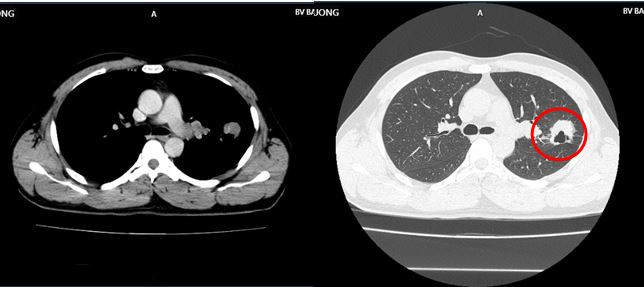

Bệnh nhân là anh H.V.H (43 tuổi) có tiền sử khỏe mạnh. Một tháng trước khi vào viện, anh H. ho khan và đau tức ngực trái. Người đàn ông này đi khám, chụp CT ngực phát hiện khối u thùy trên phổi trái kích thước 30x32mm, vài nốt mờ rải rác màng phổi 2 bên. Sau đó, anh nhập viện để điều trị.

Qua các xét nghiệm, chụp chiếu, bác sĩ chẩn đoán bệnh nhân mắc ung thư phổi trái, dạng biểu mô tuyến di căn não. Bệnh nhân được chỉ định dùng thuốc điều trị đích thế hệ thứ 2: Afatinib 40mg/ngày.

Hình ảnh CT ngực trước điều trị cho thấy u thùy trên phổi trái kích thước 30x32mm, vài nốt mờ rải rác màng phổi 2 bên. Hình ảnh CT ngực sau 9 tháng thể hiện khối u phổi phải tiếp tục giảm kích thước 16x19mm, không còn hạch rốn phổi. Hạch trung thất không còn, tổn thương di căn não đơn ổ biến mất, chất chỉ điểm khối u CEA, Cyfra 21-1 giảm về giới hạn bình thường.